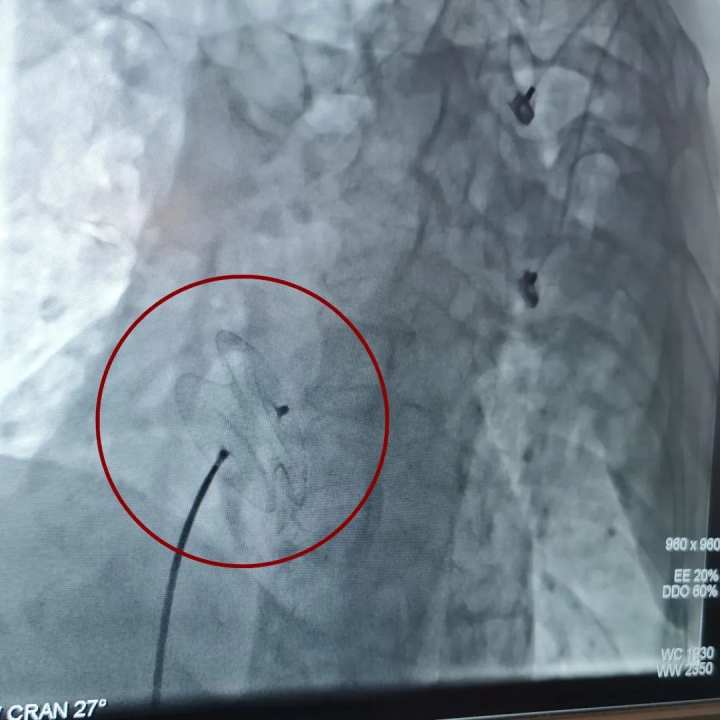

近日,杭州市一医院瓶窑院区(余杭三院)成功开展区属医院首例房间隔缺损封堵术,为患者封住心脏缺口,实现心脏介入治疗的新突破。

在杭州市第一人民医院心血管内科副主任杨建敏主任医师的指导及相关科室的全力配合下,楼朝臣带领介入团队为林阿姨在局麻下开展区属医院首例房间隔缺损封堵术。

房间隔缺损封堵术,顾名思义就是填补孔隙,采用经股静脉穿刺的方法,将封堵伞送入心房,补贴固定在房间隔缺损处,阻断房水平左向右分流,恢复正常的血液循环途径。 心血管内科主任章永根介绍,“房间隔缺损根据位置不同可分为原发孔型缺损和继发孔型缺损两类,像林阿姨这样的继发孔房间隔缺损的患者,多数在儿童时期除易患感冒等呼吸道感染外可无症状,一般到青年时期才表现有气急、心悸、乏力等。”40岁后绝大多数患者症状加重,并常出现心房颤动、心房扑动等心律失常和充血性心衰等表现,甚至会导致死亡。 若怀疑出现房间隔缺损时,应及时找专业医师听诊做出初步的判断,而后行超声心动图、胸部X线、心电图等检查进一步确诊,为治疗方案的制定提供依据。